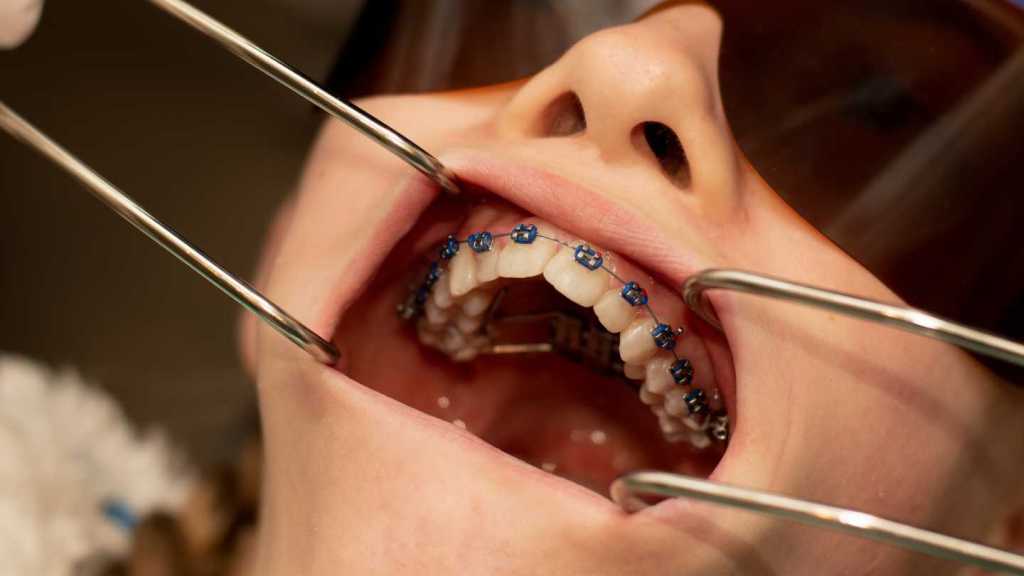

Posteriormente, o tratamento ortodôntico corretivo pode ser iniciado ou retomado, integrando a expansão ao planejamento global do caso.